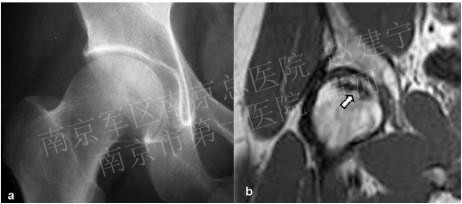

2.影像学检查: 髋部正位片及蛙式位片仍是重要的诊断手段,正位片最初的阳性表现为头下的硬化带及囊性改变,由于正位片中髋臼前后缘与股骨头上方存在重叠,有可能导致病损区显示不清,因此蛙式位片不可或缺,随着病情发展,软骨下骨与软骨分层,X片上则表现为新月征的特点;由于疾病早期X片可无阳性表现,MRI是目前诊断ONFH的“金标准”,其特征性体现在T1加权像上的低密度信号以及T2加权像的高密度信号,是坏死骨与活性骨的交界处出现大量富含血管的肉芽组织的表现。

囊性变及硬化带

新月征

T-1 W可见ONFH典型的“条带状”低信号,T-2 W可见双侧股骨头“双线征”表现,外层高信号而内层为低信号

X片无异常,但T-1 W可见典型的条带状低信号改变

平片中可见软骨下骨硬化,边缘不清;T-1 W则可清晰显示病损范围